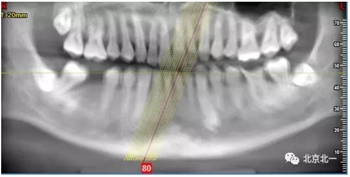

CBCT:骨量高度及寬度可, 48埋伏,低位阻生.37近中骨吸收

第一次支抗釘脫落, 第二次支抗釘位于48位置, 頰側(cè)舌側(cè)舌側(cè)扣牽引。

北一種植王明老師總結(jié):本病例難點在于設(shè)計多學(xué)科治療。 治療周期拉長, 患者智齒低位, 拔除困難, 容易造成神經(jīng)麻木。 必須由經(jīng)驗醫(yī)師主刀。 北一微創(chuàng)拔牙理念主張將牙齒進行有絲分裂, 進行智齒粉碎。 對工具要求較高。 較少患者痛苦。

正畸支抗下頜角支抗釘不僅僅考慮解剖結(jié)構(gòu), 需要考慮下頜角骨質(zhì)偏硬, 不助攻可能導(dǎo)致支抗釘無法植入。